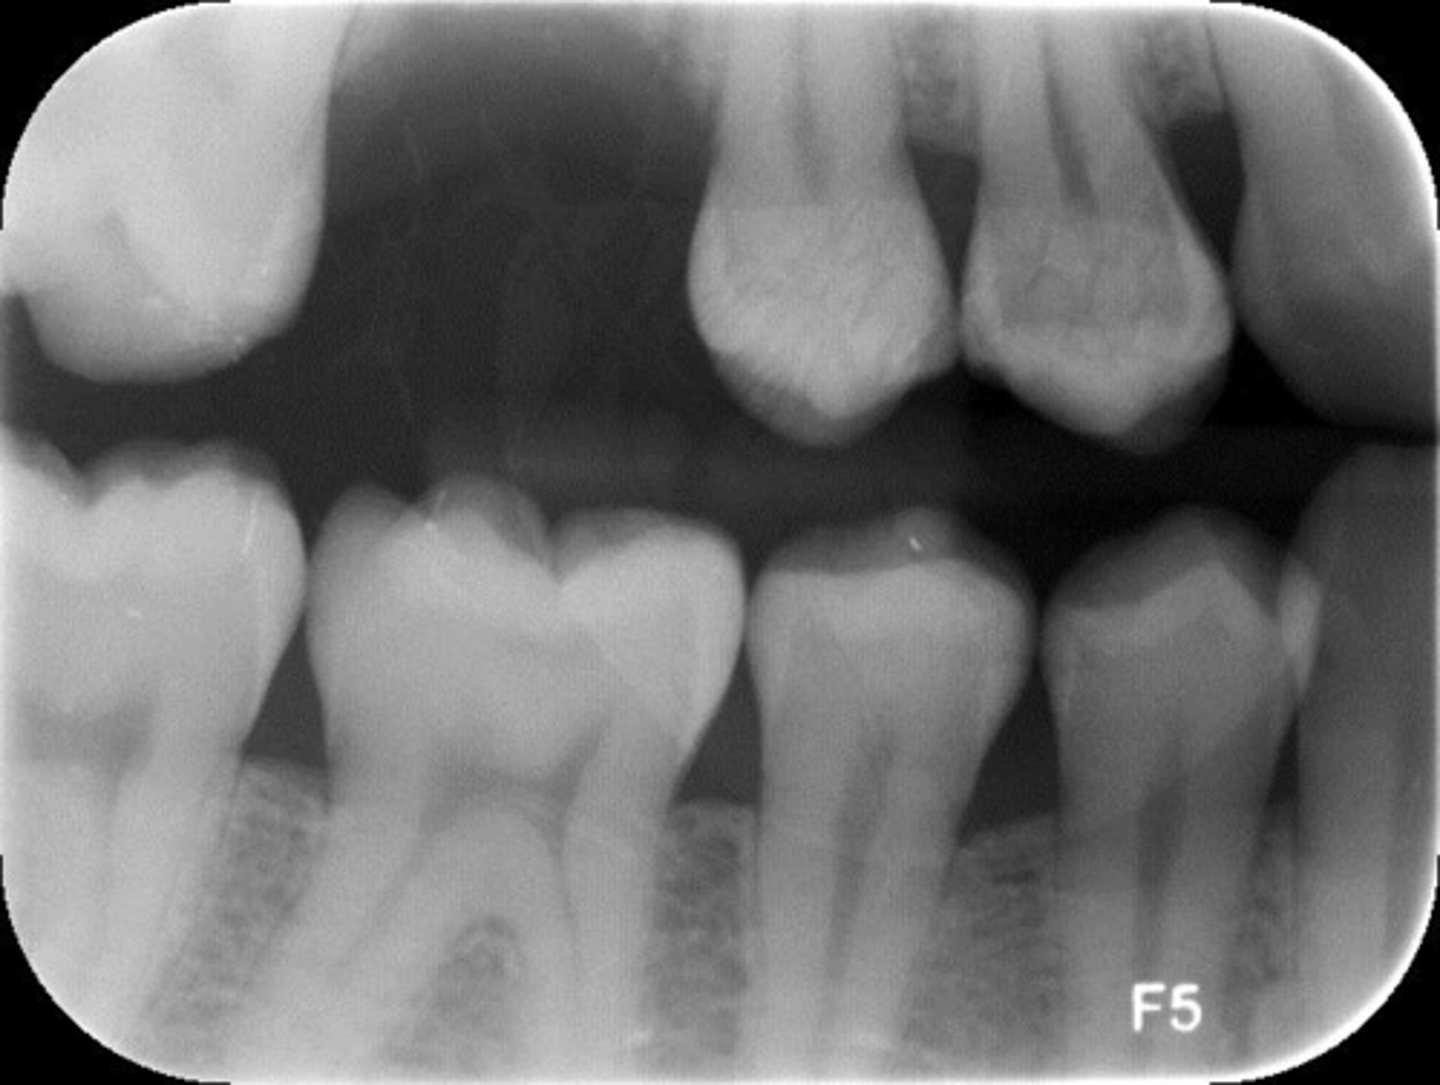

Bitewing radiograph evaluation criteria

1. No overlapping of interproximal contacts

2. Crowns centered

3. Crest of the alveolar bone should be visible

4. The occlusal plane should be horizontal

5. Buccal and lingual cusps shouldn't be separated excessively

Incorrect horizontal angulation

Appearance-Overlapped contacts or roots

Cause-Plane of plate not parallel to long axis of teeth. Central ray was not directed through inter proximal spaces.

Correction-Position plate parallel to the teeth. Direct x-ray beam through interproximal regions